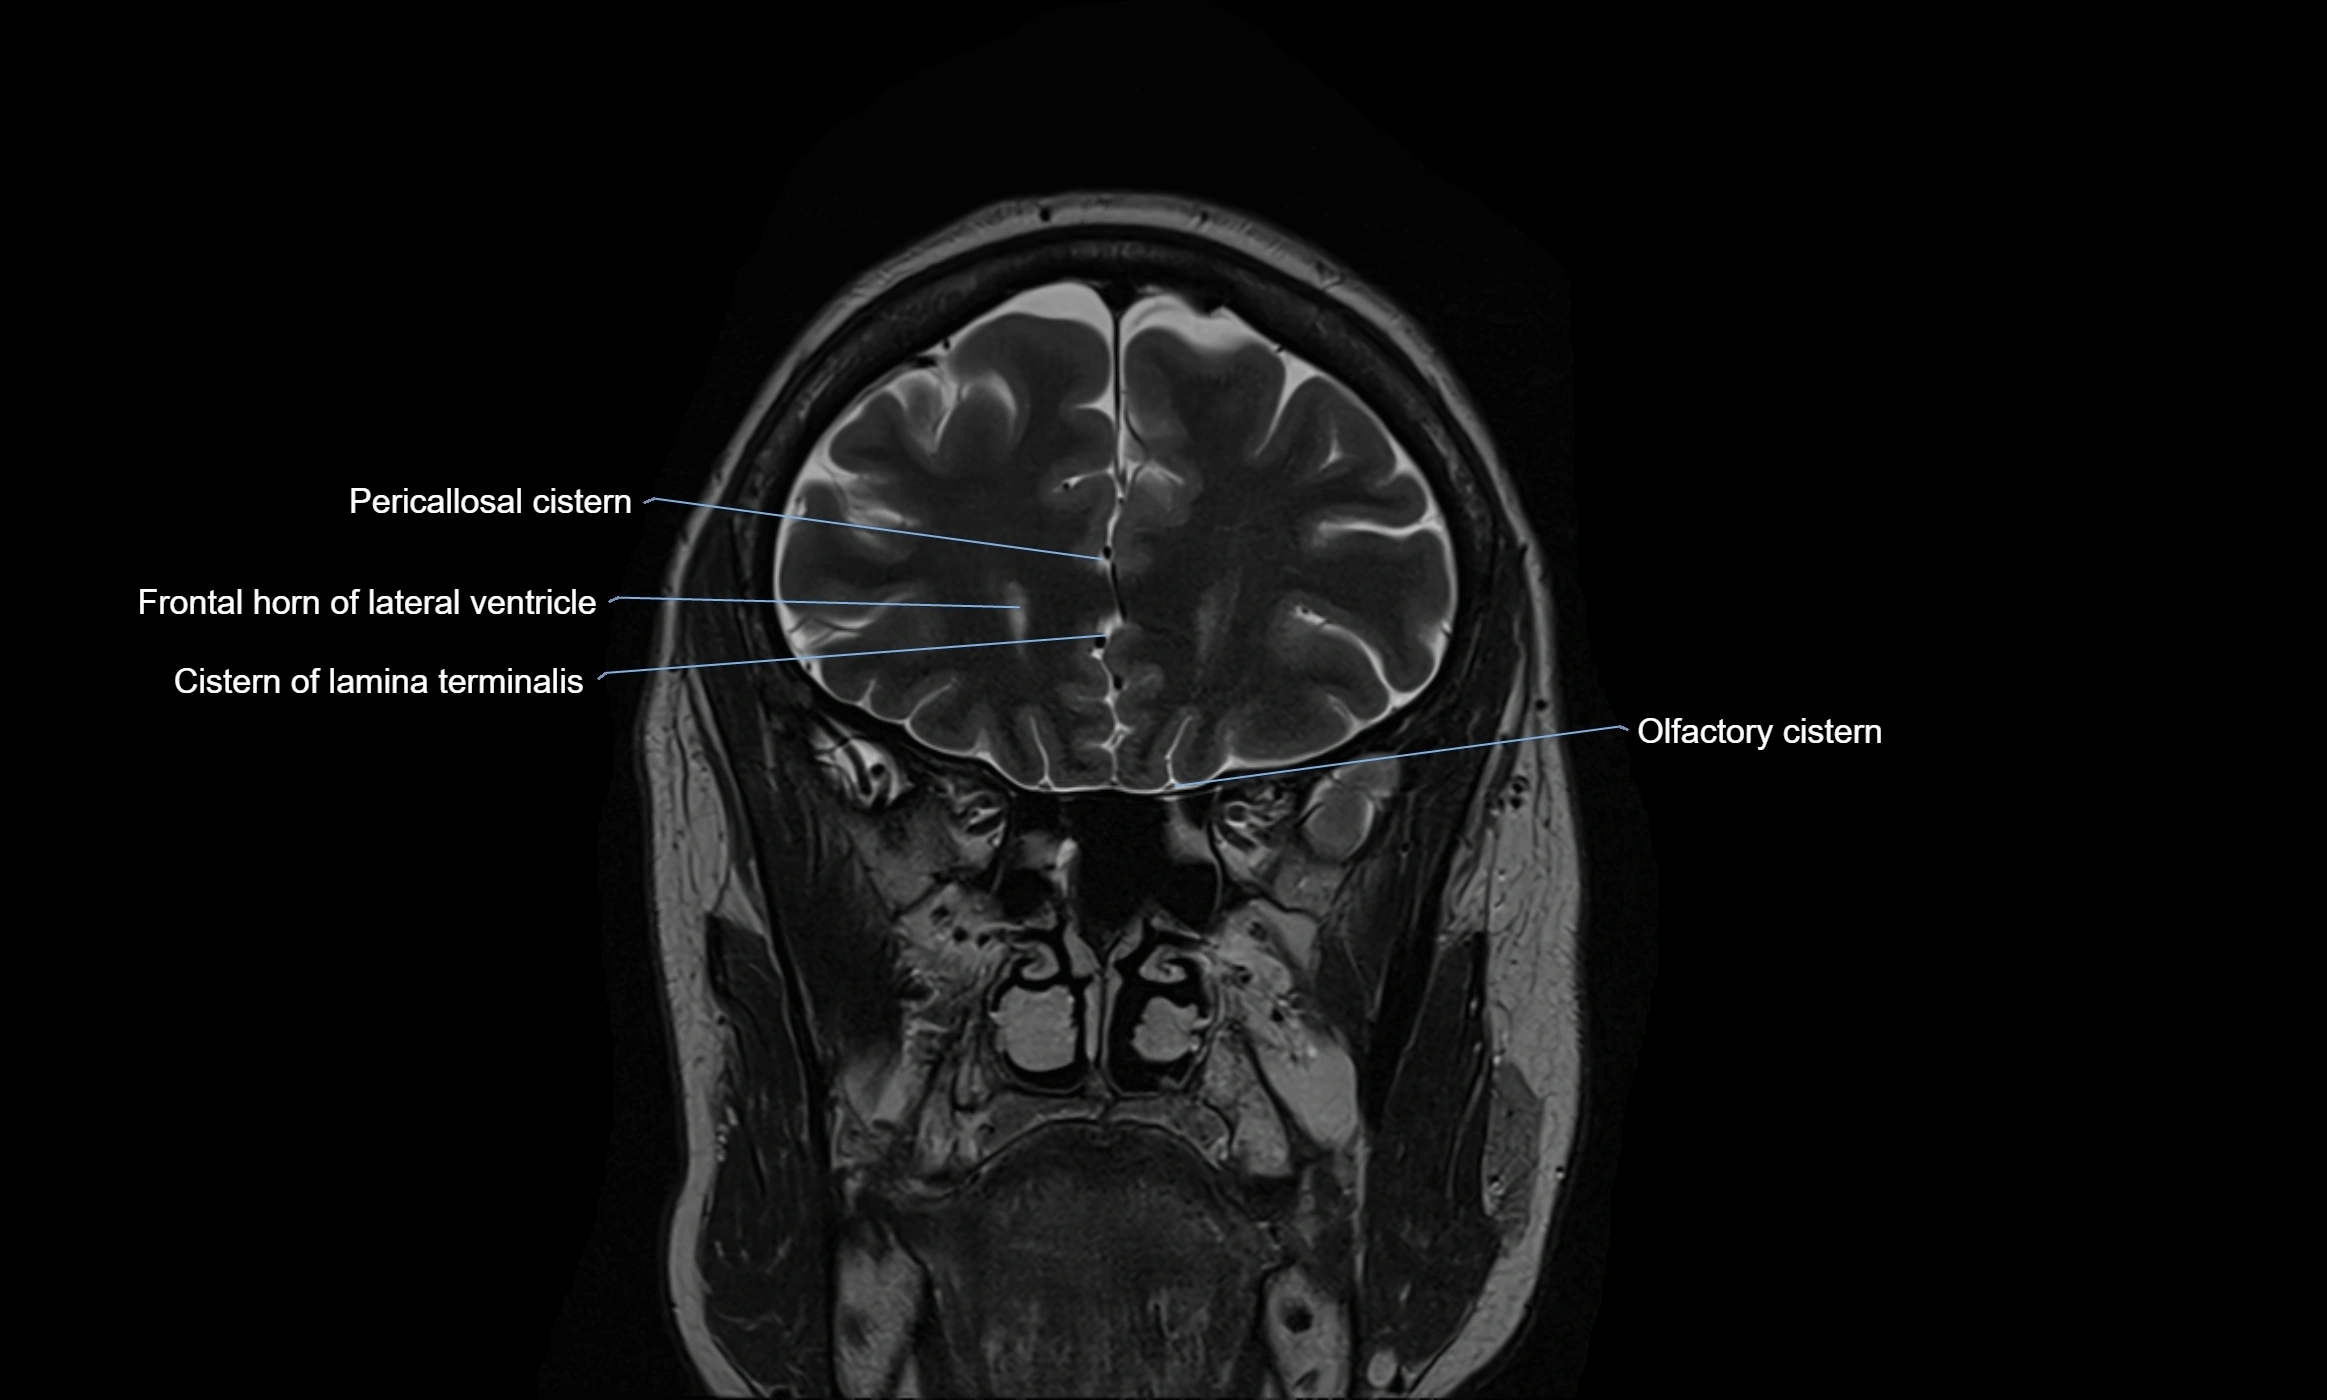

CT image

image